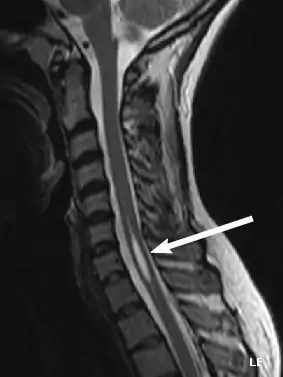

Diagnosis

Physicians now use magnetic resonance imaging (MRI) to diagnose syringomyelia. The MRI radiographer takes images of body anatomy, such as the brain and spinal cord, in vivid detail. This test will show the syrinx in the spine or any other conditions, such as the presence of a tumor. MRI is safe, painless, and informative and has greatly improved the diagnosis of syringomyelia.[14][15][16][17][18][19][20][21][22][23][24][25]

Like MRI and CT scans, another test, called a myelogram, uses radiographs and requires a contrast medium to be injected into the subarachnoid space. Since the introduction of MRI, this test is rarely necessary to diagnose syringomyelia.

Diagnostic technology is another area for continued research. MRI has enabled scientists to see the situation within the spine, including syringomyelia, before any symptoms appear. A new technology, known as dynamic MRI, allows investigators to view spinal fluid flow within the syrinx. CT scans allow physicians to see abnormalities in the brain, and other diagnostic tests have also improved greatly with the availability of new, non-toxic, contrast dyes.